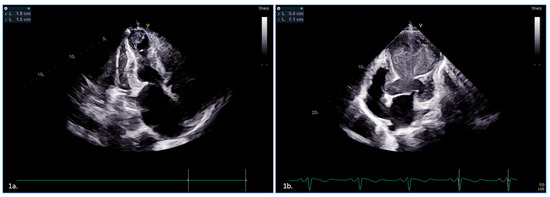

2.1. Case 1

2.2. Case 2